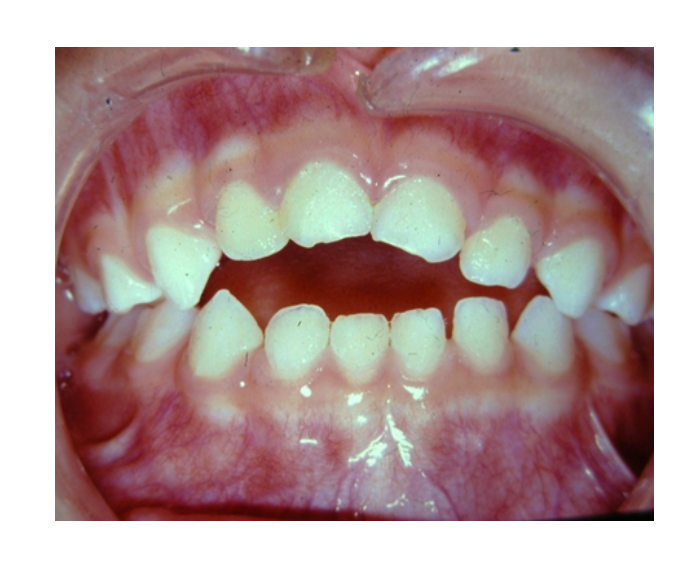

Chupadedos